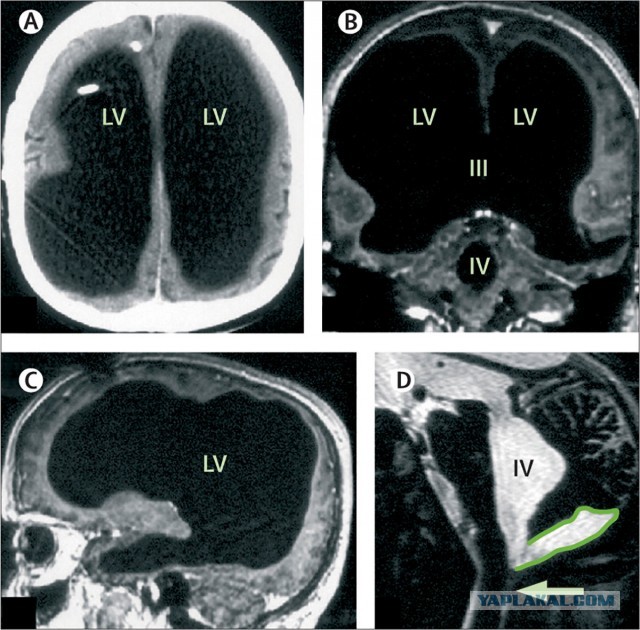

Проведенные исследования показали, что практически вся структура головного мозга Луи представляет собой жидкость, а от главного органа центральной нервной системы осталось как будто около 10% — сохранным оказался внешний тонкий слой тканей. Это видно на сканах головного мозга пациента:

Проведенные же сканы головного мозга, поясняли исследователи, выявили значительное увеличение боковых желудочков, а также третьего и четвертого (то есть всех входящих в желудочковую систему); сильное истончение коры больших полушарий; кисту в задней черепной ямке (это область вблизи основания черепа, в которой находятся мозжечок и часть ствола головного мозга).